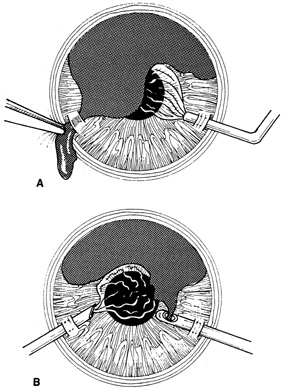

Iris incarceration and prolapse are frequently noted conditions that accompany corneal lacerations. A peaked pupil signals tissue incarceration. If prolapsed tissue is present, it must first be carefully examined. Usually, macerated, feathery, devitalized, or depigmented iris should be excised. The prolapsed tissue should be evaluated for any signs of surface epithelialization. In this case, it should be excised to prevent any epithelial cells from proliferating in the anterior chamber. In general, tissue that has been prolapsed for longer than 24 hours should be excised to avoid infection; however, if the tissue appears healthy, it may be replaced with caution. Any tissue to be excised should be gently grasped with fine forceps without applying undue traction. The tissue is then cut flush with the cornea. When excising any tissue, every effort is made to preserve as much as possible to maintain a normal iris diaphragm and conserve tissue for secondary reconstructive efforts.8

Incarcerated tissue will usually require mechanical reposition. Selected cases of mild incarceration may be treated with pharmacologic agents. Agents such as intraocular acetylcholine or carbachol cause pupil constriction, thus pulling iris from the wound. If incarcerated iris is located in the central cornea, mydriatic agents (e.g., intraocular epinephrine 1:10,000) may be used. If mechanical reposition is required, simply deepening the anterior chamber may release incarcerated tissue. Viscoelastic agents may be irrigated through the paracentesis port or the wound adjacent to the involved iris tissue in an attempt to draw the incarcerated iris from the wound (Fig. 12). If unsuccessful, a cyclodialysis spatula or irrigating canula may be passed through the paracentesis site and used to directly sweep incarcerated tissue free (Fig. 13). Care is always taken to avoid trauma to the corneal endothelium, iris, and lens. Any excised tissue should be sent to the pathology department for examination.